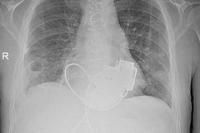

Новый тест слюны сможет определить скрытую угрозу сердечной недостаточности

Учёные разработали новый метод скрининга, позволяющий выявить скрытый риск развития сердечной недостаточности с помощью простого анализа слюны. Это серьёзное заболевание, которое возникает, когда сердце становится слишком слабым, чтобы перекачивать кровь по организму с необходимой скоростью. В отличие от остановки сердца, сердечная недостаточность поддаётся лечению, и возможна ремиссия, однако критически важным является её раннее выявление. Проблема заключается в том, что ранние симптомы часто бывают слабо выражены и их можно принять за другие состояния, поэтому пациенты нередко получают диагноз лишь на поздней стадии болезни. Существующие методы скрининга, в свою очередь, часто являются малодоступными, дорогостоящими и инвазивными.